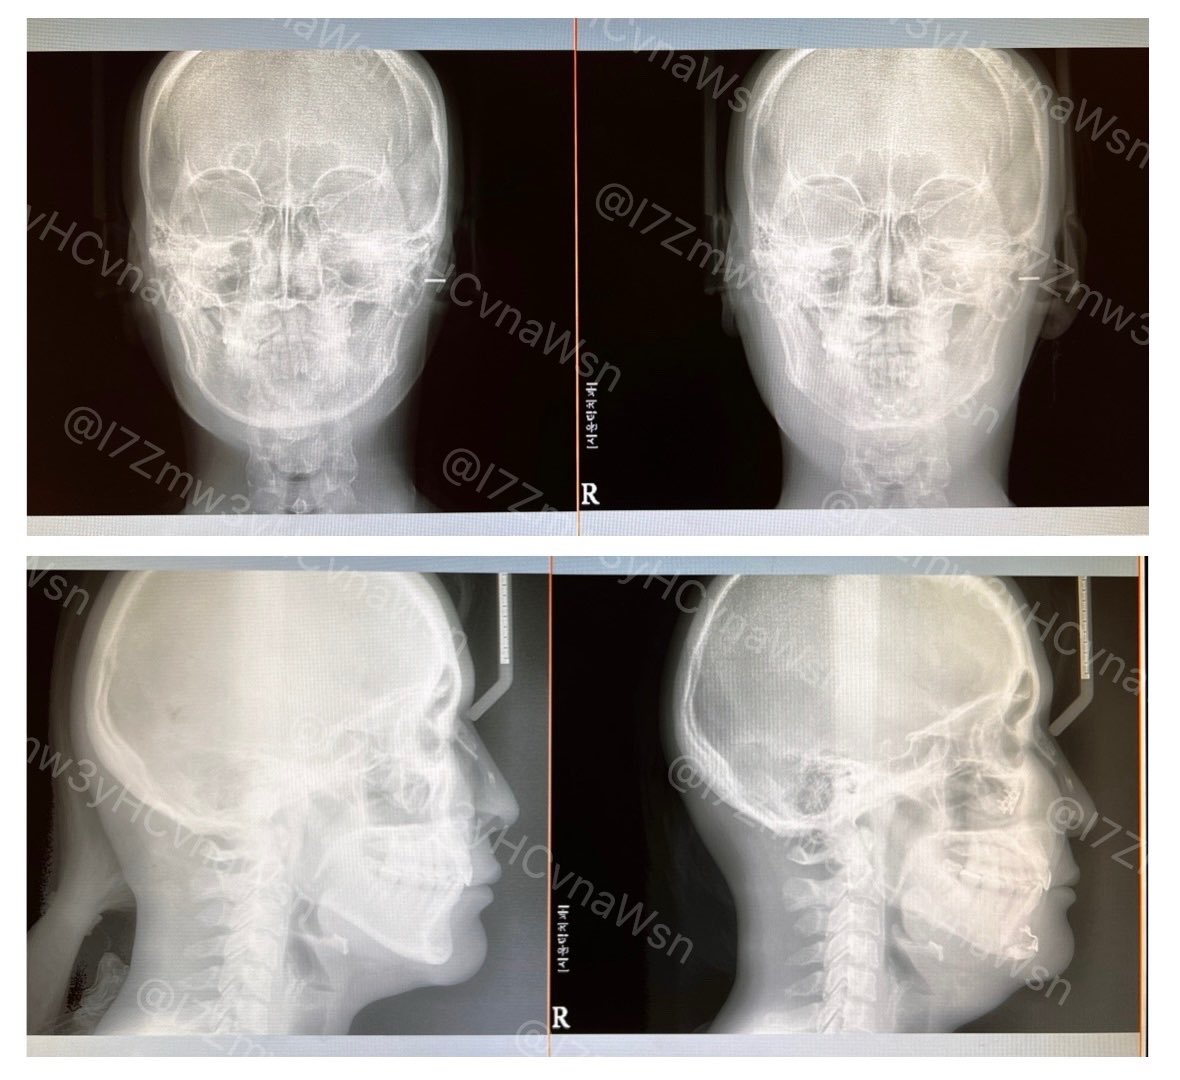

ソウルトック(@SEOULTUK)さんで受けた輪郭2.5点(頬骨+ミニV)の1週間の経過です! テープの汚れ、個人が特定しやすい特徴(ほくろ等)は加工していますが、基本無修正&ノーメイク、iPhoneノーマルカメラで撮影しています。 術後7日目に撮った🩻を見て頂くと、腫れが顕著!伸び代ありすぎ!!✨😂✨

術後7日目に撮った🩻を見て頂くと、腫れが顕著!伸び代ありすぎ!!✨😂✨

とりあえず骨だけでも…! 顎の骨部分は前回よりもさらにくっつき、またミニV…というには申し訳ない、下顎角だけしっかり残して、そこから顎までのラインはしっかり切って頂いたところも切った感が薄れ、丸みが出てきていました! この内容もまたちゃんとポストしますが、ひとまず!!

顎の骨部分は前回よりもさらにくっつき、またミニV…というには申し訳ない、下顎角だけしっかり残して、そこから顎までのラインはしっかり切って頂いたところも切った感が薄れ、丸みが出てきていました!

この内容もまたちゃんとポストしますが、ひとまず!!

6ヶ月の経過があげられないうちに、7ヶ月になってしまい申し訳ないです…!! 今週末までめちゃくちゃ忙しいので、終わり次第アップします!!!😭